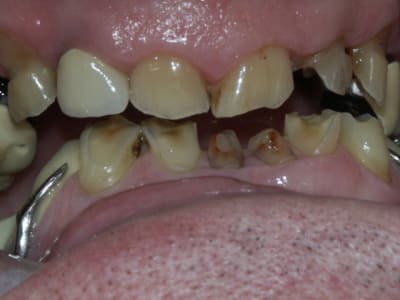

Après il faut raisonner par sextant et ne pas hésiter à faire le ménage dans les secteurs trop compromis: 14 à 18 me paraissent bonne pour le cimetière des dents, de l'autre côté c'est à confirmer par des rétros mais ça n'a pas l'air beaucoup plus glorieux; en bas les secteurs postérieurs ne sont pas terribles non plus si tu considères que la première molaire secteur 3 n'est pas conservable, tu peux abandonner la deuxième aussi; secteur 4 ta molaire pourrait te servir d'appui pour une éventuelle PAP.

Avec des PAP, je garderai les trois quatre dents conservables en bas en antérieur avec une barre.

En haut, c'est à toi de voir si tu peux faire un bridge de 14 à 24, où garder les racines en appui comme en bas.

Pour la DV, une fois que toutes les dents égressées ont été retirées, je ne pense pas que tu auras de problème de place particulier, à confirmer avec les modèles (il faut juste compenser la perte de substance des molaires mandibulaires).

première chose a faire amha, est de surélever jusqu'a bonne hauteur et contrairement a ce que tu as dit ,je pense qu'une petite surrelevation posterieure donne une surrelevation antérieure plus importante!

j'ai deja eu des cas plus ou moins semblables et tout est fait en provisoire avant de s'engager dans des definitifs

*J'essayerais de tracer une courbe de Spee en haut en meulant les dents egressées,

* j'augmenterais la hauteur en réhaussant les dents sur le stellite,(essais d'occlusion jusqu'a avoir bon espace et confort ,)

*les incicives du bas compos ou provisoires

*Chercher hauteur et occlusions adequates

*Seulement ensuite envisager au cas par cas quoi faire pour le haut